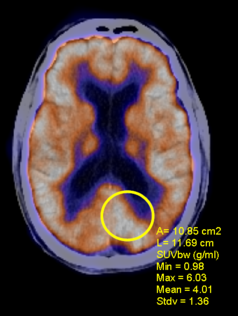

3.      Click & drag the mouse on the image to calculate the SUV for that region, as shown below: